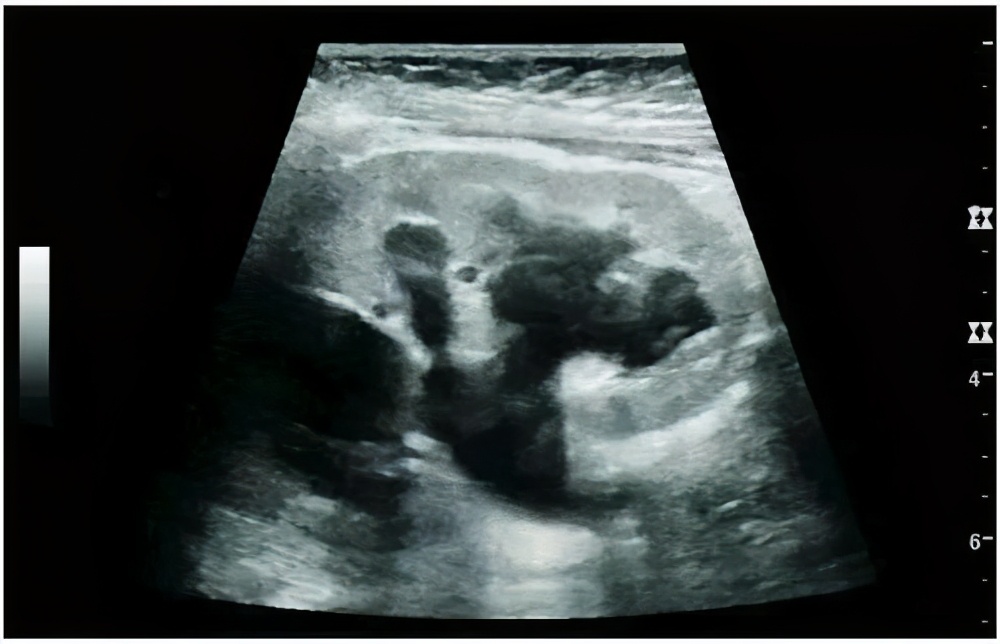

我们平时在门诊见的最多的情况是因为健康体检或是其他科室就诊查腹部B超时候发现的肾积水,1)腹部B超是我们筛查肾积水的首选方法,简单、无创;即使是孕妇、胎儿、甚至肾衰竭的患者也可以检查。

肾脏B超可清晰显示肾积水情况,明确有无结石,了解肾盂、肾盏等结构,简单、方便、无创

肾脏B超显示,肾盂分离<10mm为正常情况,部分人在憋尿情况下可能出现10-20mm左右的肾盂分离情况,可以在不憋尿时候在复查B超;如果B超仍然提示肾盂扩张≧10mm或存在肾盏扩张则称为肾积水。

⑴轻度肾积水:肾脏形态大小多无明显异常肾实质厚度及回声正常肾集合系统分离20-30mm;⑵中度肾积水:肾体积轻度增大、形态饱满、肾实质轻度变薄、肾柱显示不清晰,肾盂肾盏均有扩张,肾盂集合系统分离30-40mm;3)重度肾积水:肾脏体积增大、形态失常、肾实质显著变薄或不能显示,甚至整个肾区均为液性暗区。